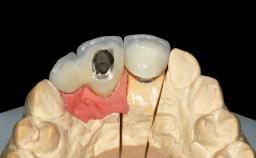

Replacement of Four Incisors with a Fixed Partial Denture on Two Narrow-Neck Implants after Implant Failure

| # of Implants | 2 |

| Prosthesis Type | FDP |

| Retention | Screw-retained, with splinted implants Screw-retained, with splinted implants |